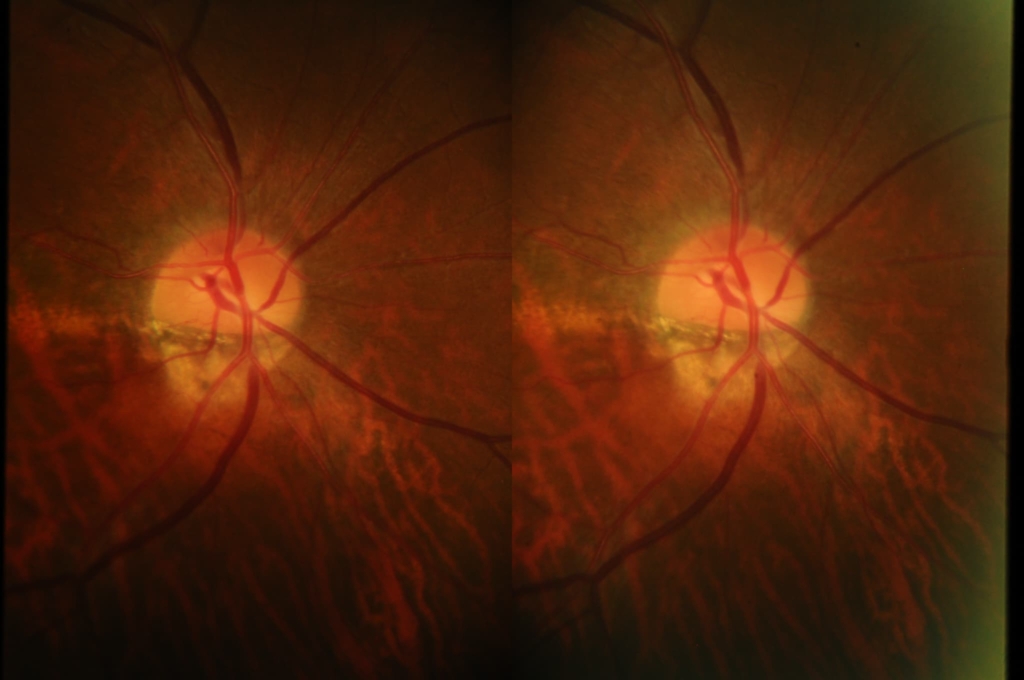

乳頭が下鼻側に傾斜し、下方に萎縮(PPA)がみられる。

両眼ともに、後部ぶどう腫staphylomaの上縁に一致して乳頭下縁から黄斑を横断するように帯状の網脈絡膜の萎縮巣がみられる。また後部ぶどう腫領域に一致して網膜・脈絡膜が菲薄化しているため、紋理眼底tessel lated fundusがみられる。